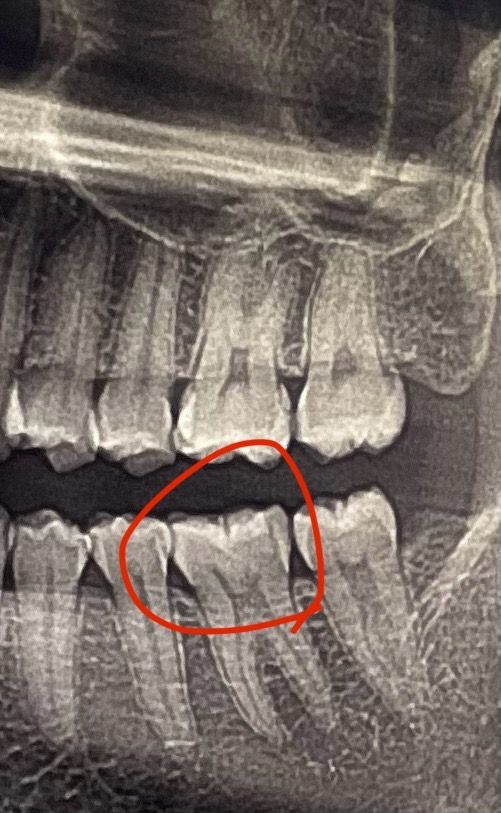

오늘 치과 갔다왔는데 이부분에 충치가 있을 거라고 생각했는데 예상 외로 다른 곳에 충치가 있다고 해서 치료 받고 왔어요 의사선생님께 여쭤본다는 걸 너무 긴장해서 못 물어보고 그냥 나왔는데 여기엔 아무런 문제가 없나요...?

엑스레이 상으로는 충치가 잇는것처럼 보이지만 치료를 한곳의 재료 때문에 저렇게 보이는 경우가 있습니다. 아마 충치엿다면 육안으로도 보엿을꺼에요.

방사선사진상으로는 정확한 확인이 어려워 보입니다.

뒤에 부분에 파절이 보이는것 같기도 하지만 정확한 확인을 위해서는 육안으로 확인해야 합니다.

충치의 가능성은 있어보이지만 위 사진 하나만 가지고는 진단을 하기에는 무리가 있어보입니다.